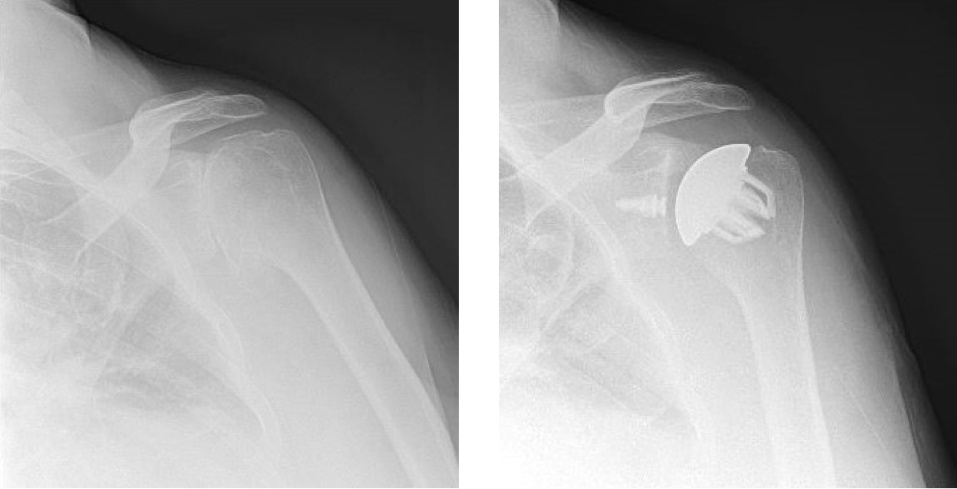

Pre-operative and post-operative xrays of a patient with humeral head avascular necrosis, treated with hemiarthroplasty surgery.

Partial shoulder replacement usually involves only replacing the ball side or humeral head, and it is termed a shoulder hemi-arthroplasty. In this procedure, the ball is replaced with a metallic head and the socket is left alone. This can be performed in very young patients with shoulder arthritis, fractures of the humeral head, and for pathology specific to the humeral head like avascular necrosis.